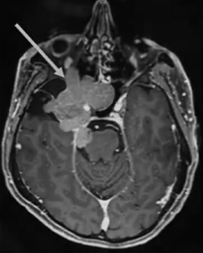

患者術(shù)前影像。(A)術(shù)前軸位T1加權(quán)釓增強(qiáng)磁共振成像(MRI),顯示腦膜瘤延伸至后顱窩、海綿竇、眼眶和蝶竇。(B)腫瘤延伸至中顱窩、翼腭窩和顳下窩。(C)術(shù)前軸位計(jì)算機(jī)斷層掃描(CT)顯示蝶骨大翼侵蝕和蝶竇受累。